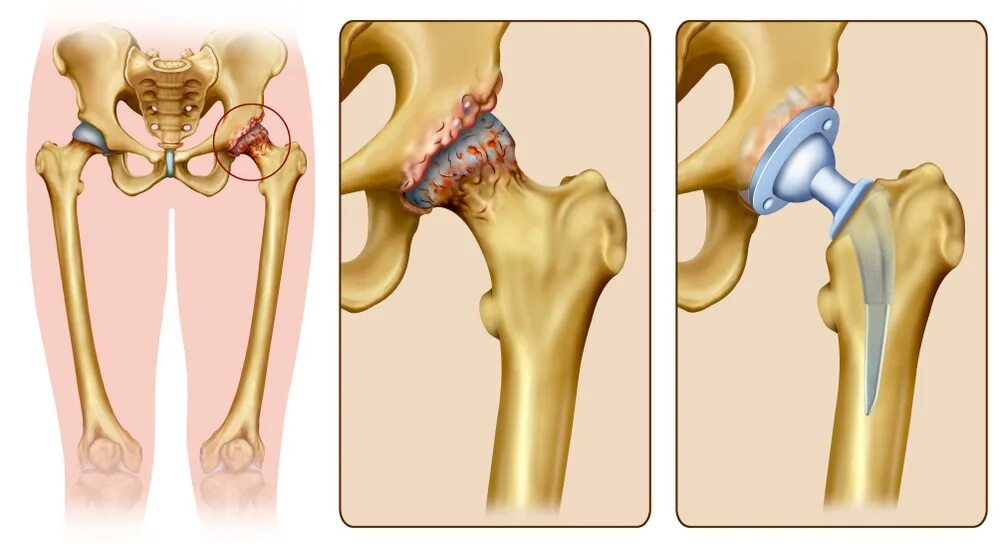

Тазобедренный сустав 3 степени лечение